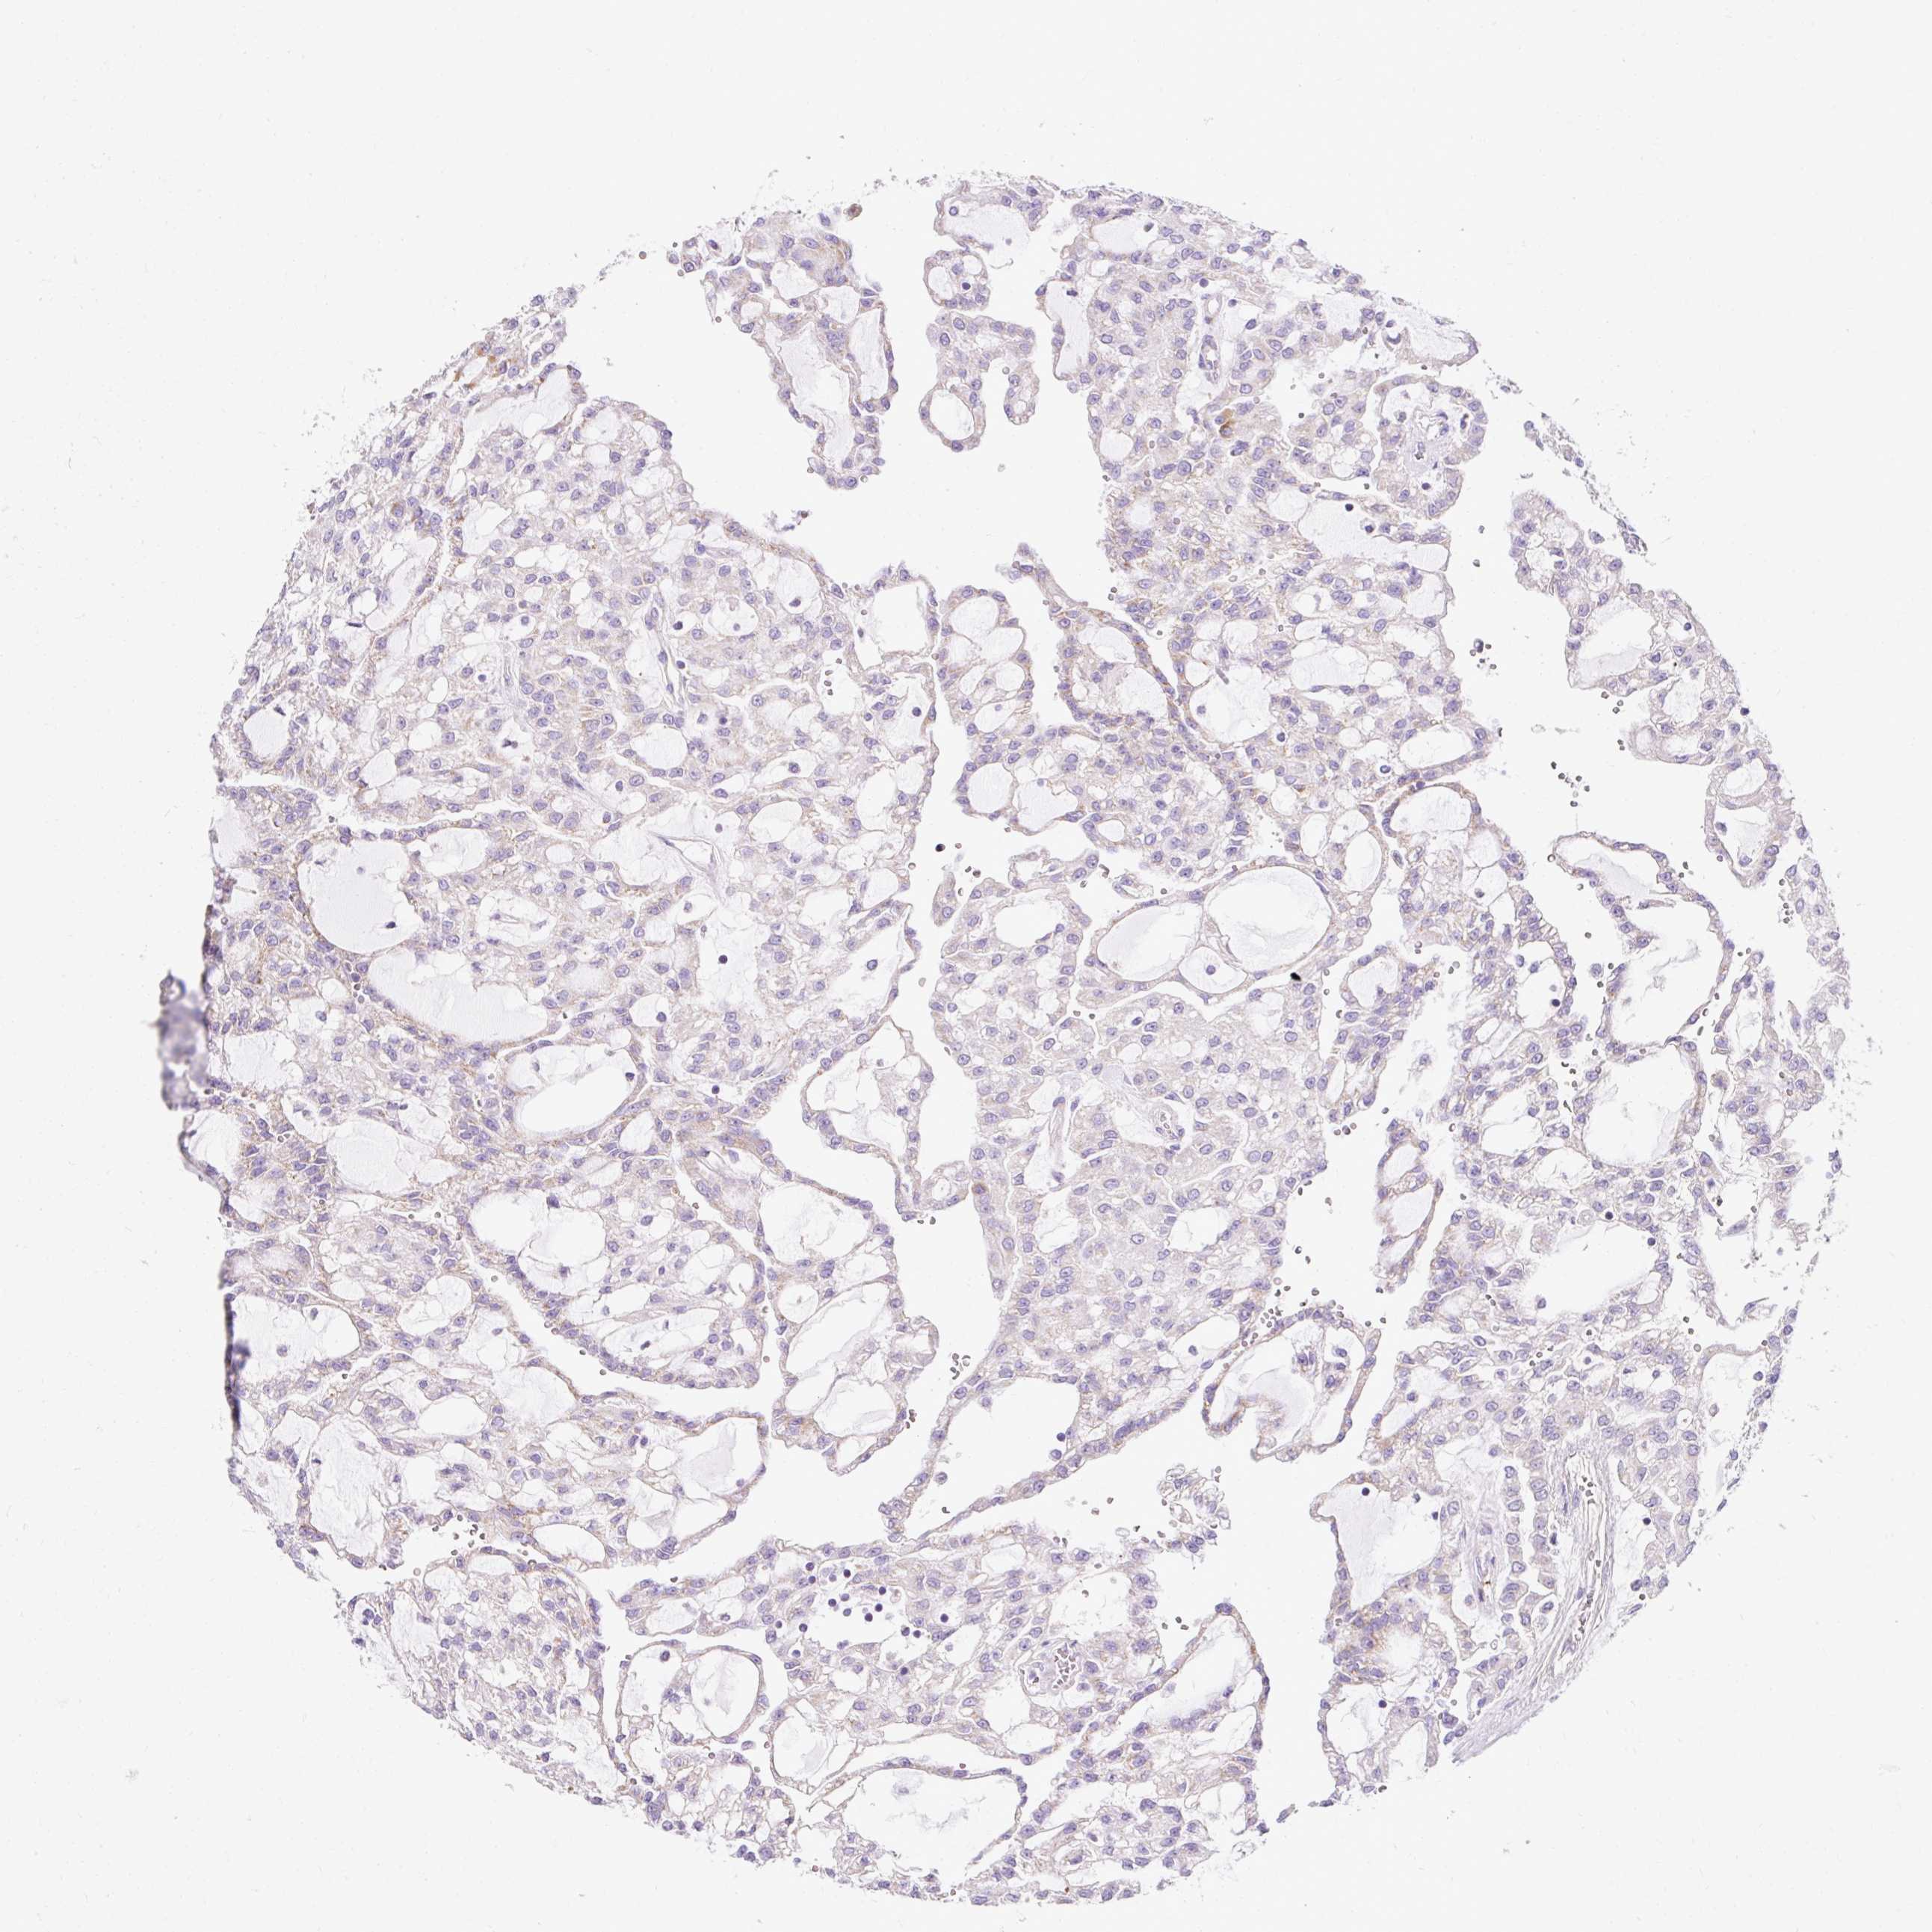

Renal cancer

Kidney renal clear cell carcinoma